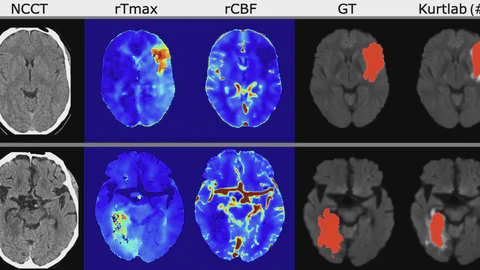

I am a PhD Candidate at the Mechanical Engineering Department of the University of Washington working with Mehmet Kurt, supported by the DoE Computational Science Graduate Fellowship (CSGF). My research interests include AI for medical imaging, with a focus on segmentation, generative modeling, and deep learning surrogates to accelerate physics inverse problems. Previously, I gained research experience through internships at Lawrence Berkeley National Laboratory, Los Alamos National Laboratory, and the Air Force Research Laboratory. I am also proud to be the co-chair of the COMPASS seminar series, a student-led online event that brings together students and professionals from various disciplines related to artificial intelligence (AI) and medical imaging.